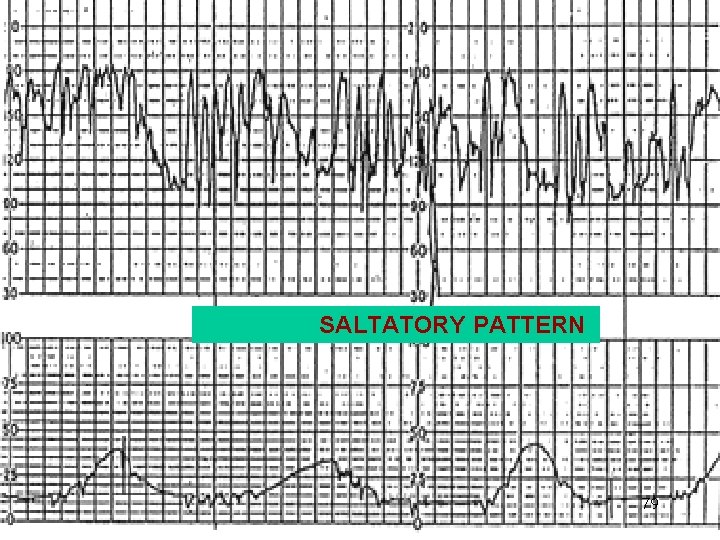

SALTATORY PATTERN 79